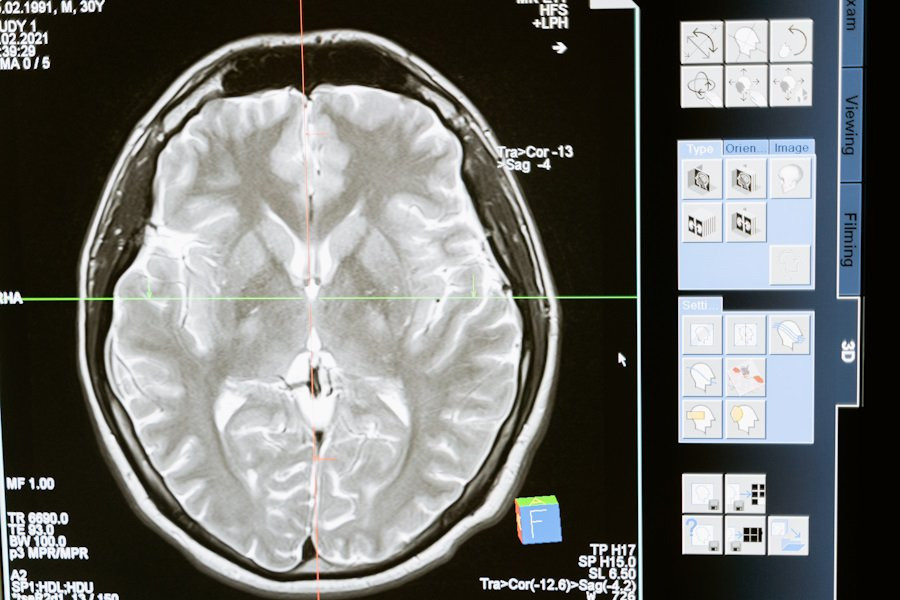

Исследователи из Institute for Basic Science (IBS) (Республика Корея) провели успешные испытания новой методики Magnetogenetic Interface for NeuroDynamics (Nano-MIND), которая позволяет воздействовать на мозг человека без использования имплантатов. Эта технология объединяет магнитные поля и намагниченные наночастицы, что открывает новые возможности для нейромодуляции, сообщает портал Nature.

Технологии нейромодуляции играют ключевую роль в исследовании связей и функций мозга. Магнитная нейромодуляция предлагает беспроводную и удаленную глубокую стимуляцию мозга, что делает её уникальной по сравнению с оптогенетикой и проводными электродами. Ранее использование магнитных подходов было ограничено из-за недостаточного понимания их работы и плохо спроектированных систем.

Методика Nano-MIND использует намагниченные наночастицы и технологию Cre-loxP для избирательной активации генетически закодированных ионных каналов Piezo1 в целевых популяциях нейронов. Это позволяет точно контролировать активность нейронов глубокого мозга как in vitro, так и in vivo.